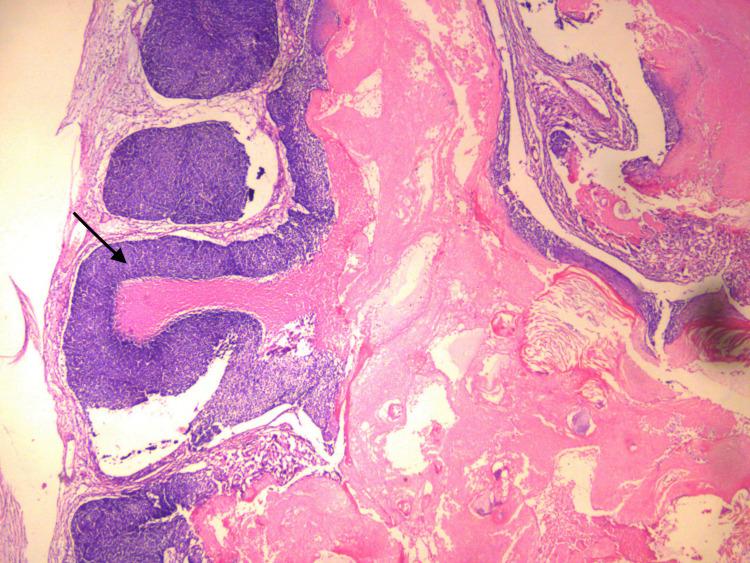

Pilomatrixoma: a review of 346 cases.

Pilomatrixoma: clinicopathologic study of 51 cases with emphasis on cytologic features.